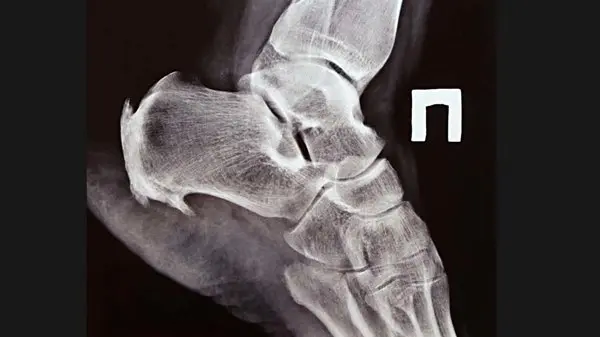

ایجاد توده دردناک در محل آسیب که پس از مدتی دردی وجود نداشته و توده کوچک و سفت می شود. تغییرات در حرکت طبیعی استخوان، ضعف، بی حسی و یا خارش در بازوها و پاها و گرفتگی عضلاتی علائم این عارضه است استخوان سازی نا به جا را می توان در رادیوگرافی ساده مشاهده نمود در اسکن رادیوایزوتوپ نیز می تواند این عارضه را زودتر از رادیوپرافی ساده تشخیص دهد .

نحوه تشخیص خار استخوانی توسط پزشک

سی تی اسکن

ام آر آی

تست های الکتروکانداکتیو